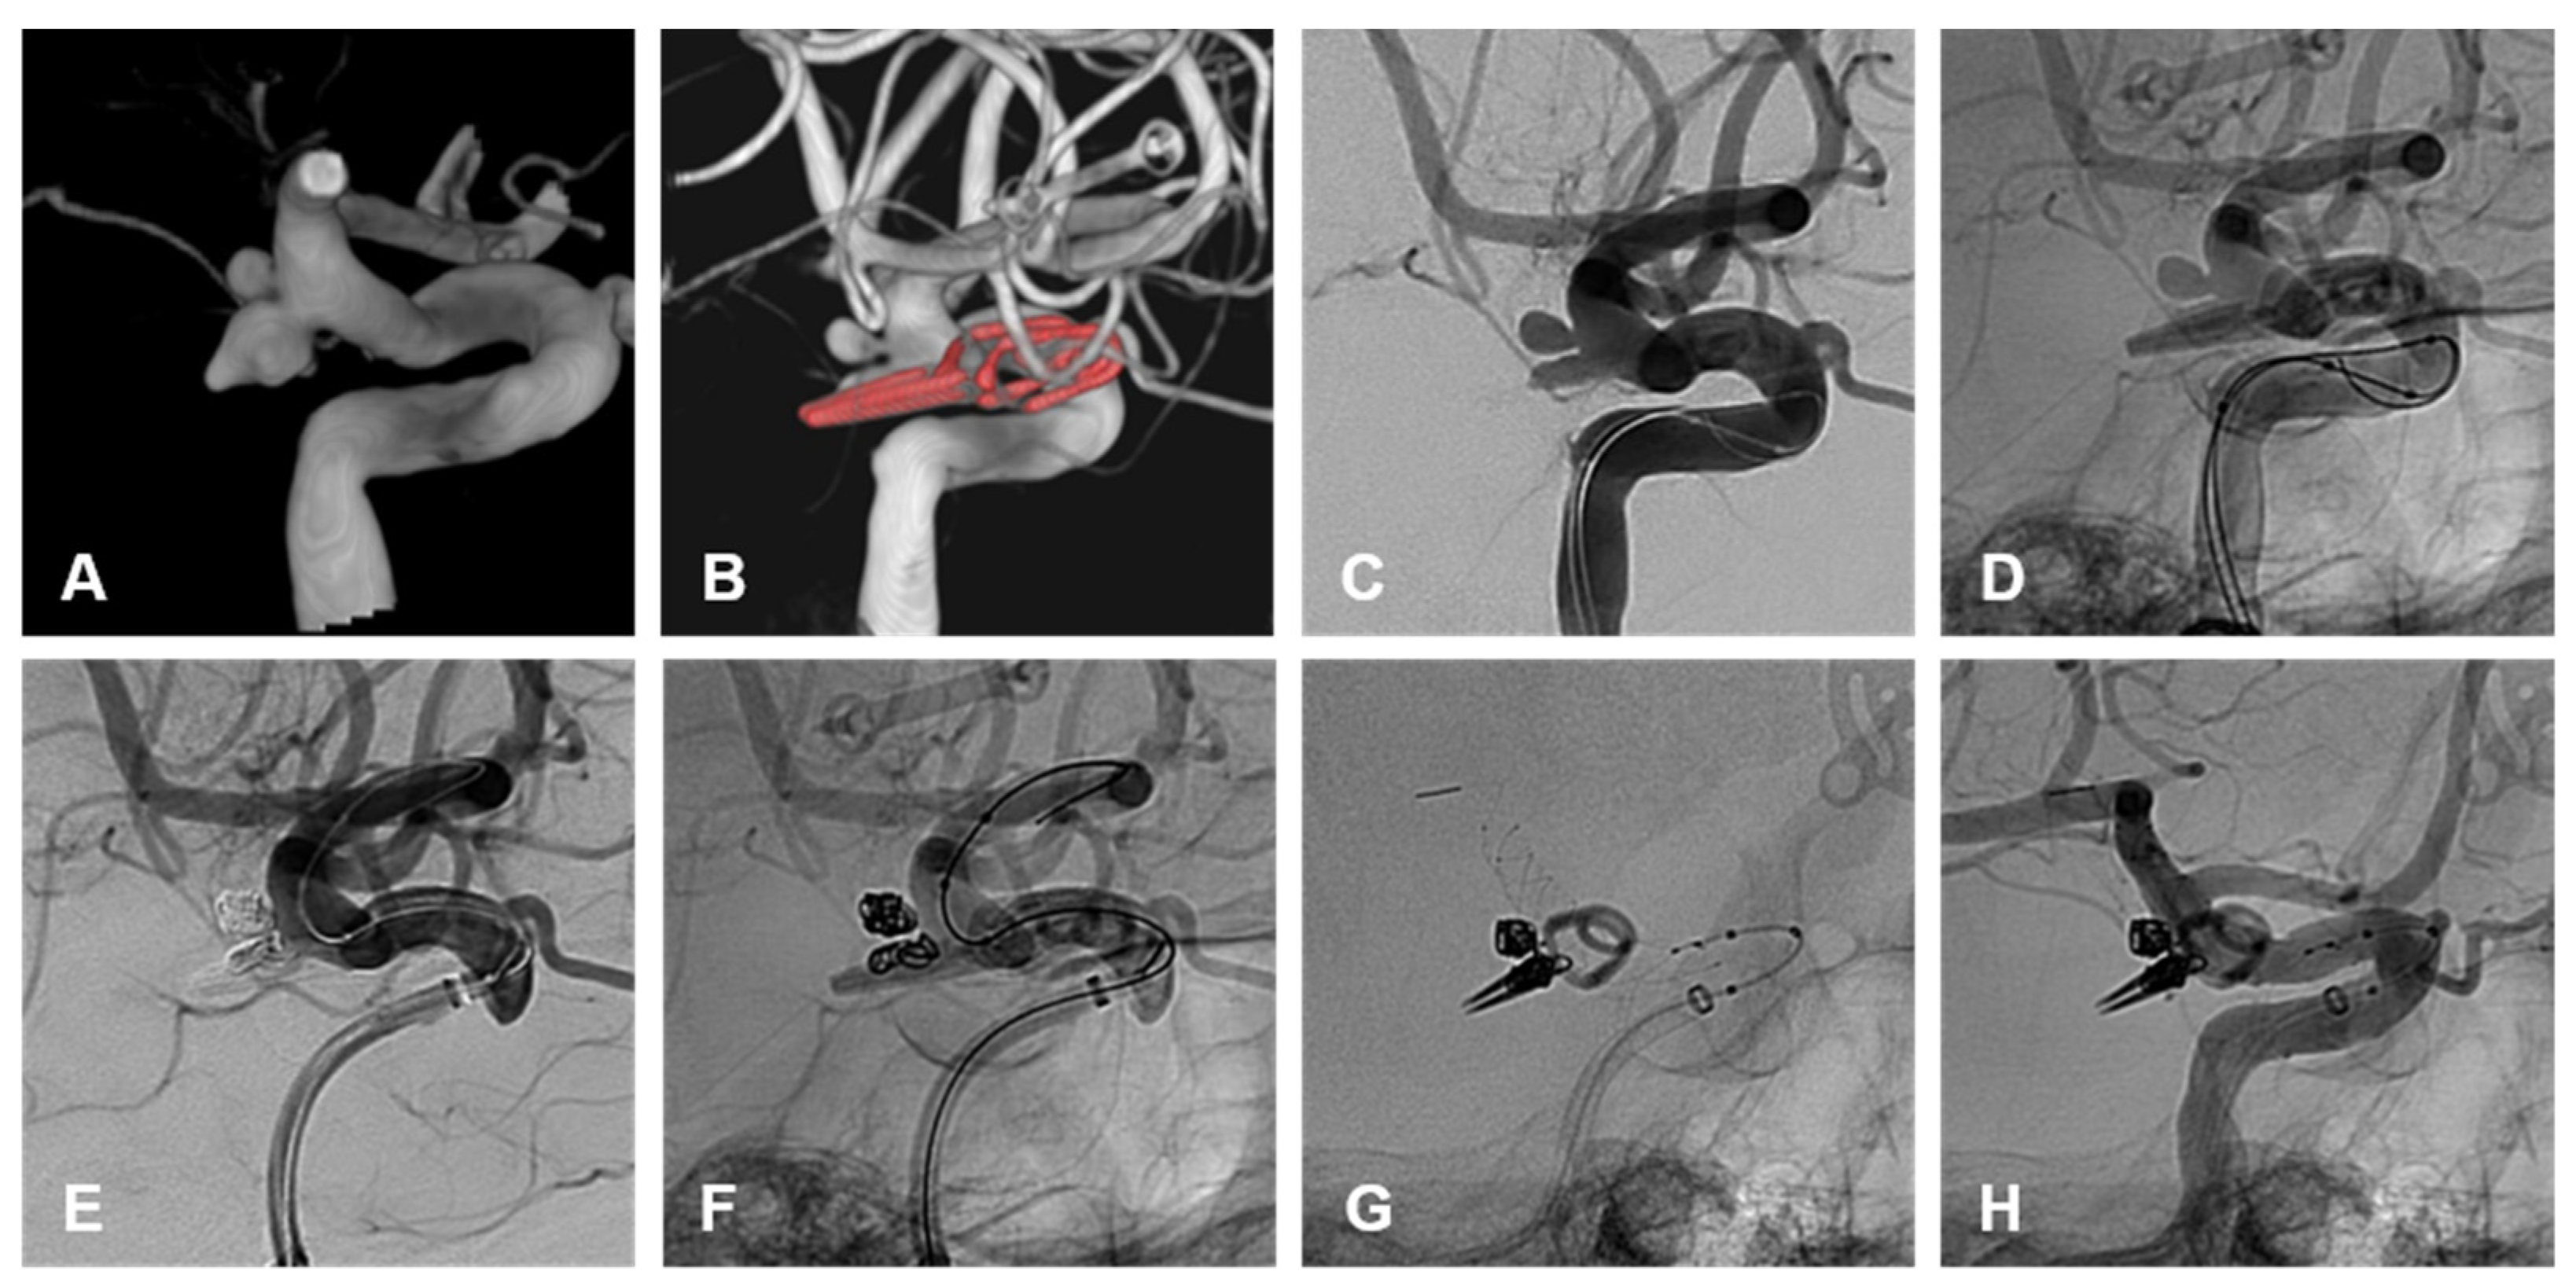

Within the endovascular cohort, one patient had an AChoA territory infarct (Figure 1) and the other had a catheter-related PCA (posterior cerebral artery) and MCA (middle cerebral artery) territory infarct. The catheter-related infarct presented with limb hemiparesis after 4 h, which resolved after 1 week.

Within the clipping cohort, both patients had AChoA territory infarcts. The post-procedural mRS were 5 and 3, respectively (Figure 2).

3.4.2. Recurrence and Retreatment

A total of 6/31 patients (19%) were retreated while 25/31 (81%) did not have a recurrence or need retreatment. Within the endovascular cohort, 3/24 (12.5%) patients required retreatment and 21/24 (87.5%) did not require any further treatment on follow-up (Table 3). Of those requiring retreatment, 2/3 (66%) were ruptured on initial treatment (Figure 1). One patient was initially treated with primary coiling and retreated by flow diverter stent, following recurrence after 5 months. The second patient was initially treated with primary coiling and was retreated with clipping due to recurrence after 3 months. Of these, 1/3 (33%) were unruptured on initial treatment with primary coiling and were retreated with a flow diverting stent (Figure 3).

Within the clipping cohort, 3/7 (43%) patients required endovascular retreatment and 4/7 (57%) patients did not require any further treatment on follow-up. Of those requiring retreatment, 2/3 (66%) were ruptured on initial treatment with clipping and required endovascular retreatment. One patient was an immediate post-clipping residuum requiring primary coiling and the second patient reoccurred after a year and required a combined balloon and stent-assisted coiling. The third patient requiring retreatment was unruptured on initial treatment with clipping and required endovascular retreatment with BAC and FDS. This recurrence occurred >10 years post-clipping and was identified on routine surveillance for additional unsecured intracranial aneurysms.

All recurrences opted for endovascular retreatment with a variety of different endovascular approaches. None of these retreatments required further treatment on follow-up. This preference for endovascular retreatment suggests that the varied armamentarium of endovascular approaches makes it malleable to altered anatomy and possibly less favorable surgical conditions with AChoA aneurysm treatment. This includes the protective micro catheter technique, remodeling with balloons, and reconstructive techniques, using stents and flow diverters. These techniques would be suitable for primary and/or secondary treatment of these aneurysms [3,4,16] (Figure 4).

Figure 4. (A) demonstrates a 3D shaded surface display of a ruptured irregular AChoA aneurysm with a posteriorly pointing nipple thought to be the rupture point. Note is made of an additional unruptured aneurysm cranial to this. The patient underwent surgical clipping of the ruptured AChoA aneurysm and remodeling of the neck to preserve the AChoA origin. (B) The patient developed an enlarging residuum on routine surveillance imaging 52 months after initial treatment. This panel demonstrates a 3D shaded surface display of the clip partly obscuring the recurrence. Note is made of the location of both aneurysm necks, which are posterior to the ICA and not visualized adequately from a sub frontal approach. (C,D) are unsubtracted and subtracted lateral angiographic images demonstrating the recurrent AChoA aneurysm and the additional untreated and unruptured aneurysm cranial to this. The patient underwent elective re-treatment with balloon assisted coiling of both aneurysms, the results are seen on the subtracted and unsubtracted angiographic images (E,F). A braided stent was deployed within the ICA, across both aneurysm necks, to promote endothelialization. This is demonstrated on the unsubtracted final angiographic images (G,H).